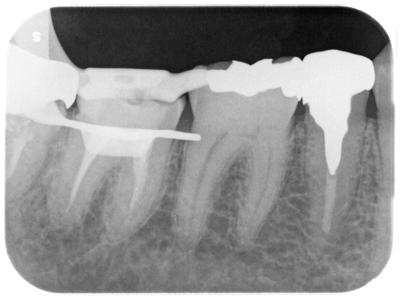

術前

隔壁等なかったので、当院で築成、ラバーダムクランプをかけたとこと。

根管充填不良が確認できる。

もっとも、レントゲン的に根尖まで充填されていることが大事ではないが。